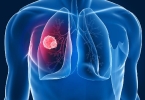

• 癌性和结核性胸水鉴别

癌性和结核性胸水鉴别

癌性胸水和结核性胸水可通过外观、生化指标、细胞学检查及病原学检测进行鉴别。癌性胸水多由肺癌、乳腺癌等恶性肿瘤转移引起,结核性胸水则与结核分枝杆菌感染相关。癌性胸水通常呈血性或淡黄色,黏稠度较高,葡萄糖 ...